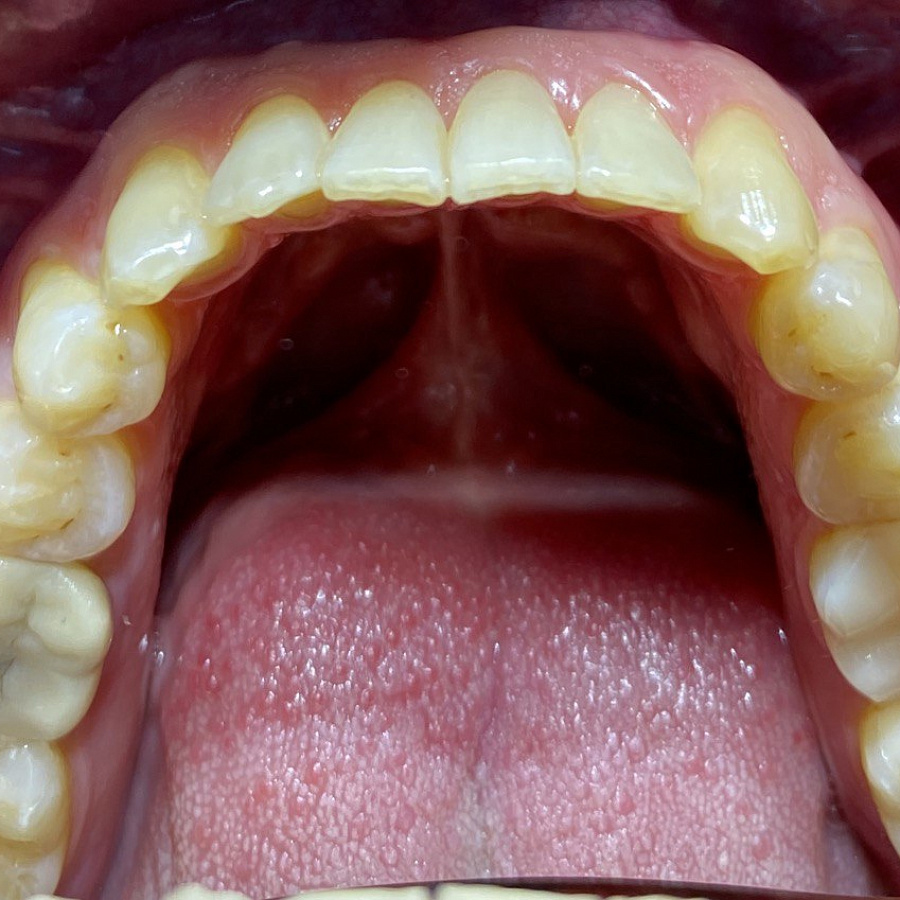

Пациент обратился с жалобами на неровные передние зубы верхней и нижней челюстей.

Диагностика показала:

• сужение зубных рядов,

• обратное перекрытие в области фронтальных зубов слева,

• разворот по оси передних зубов верхней и нижней челюстей,

• стираемость эмали зубов,

• индивидуальную микродентию 12 и 22 зубов.